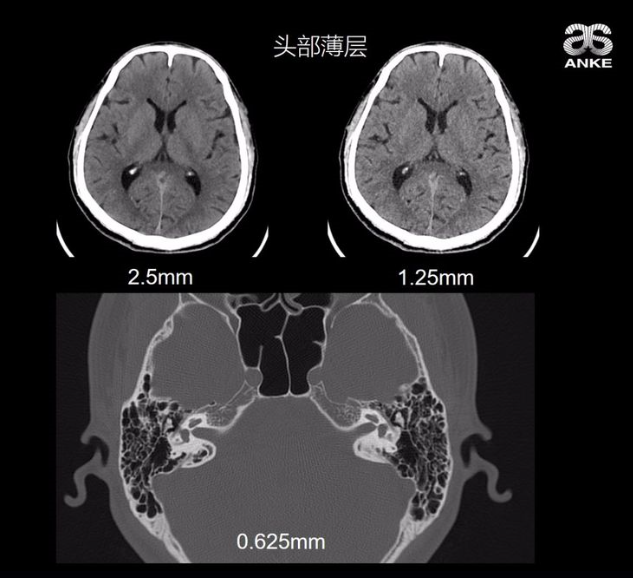

接着,吴小页博士为我们展示了多组CT成像的应用效果图,以及参数改变下的效果对比图。